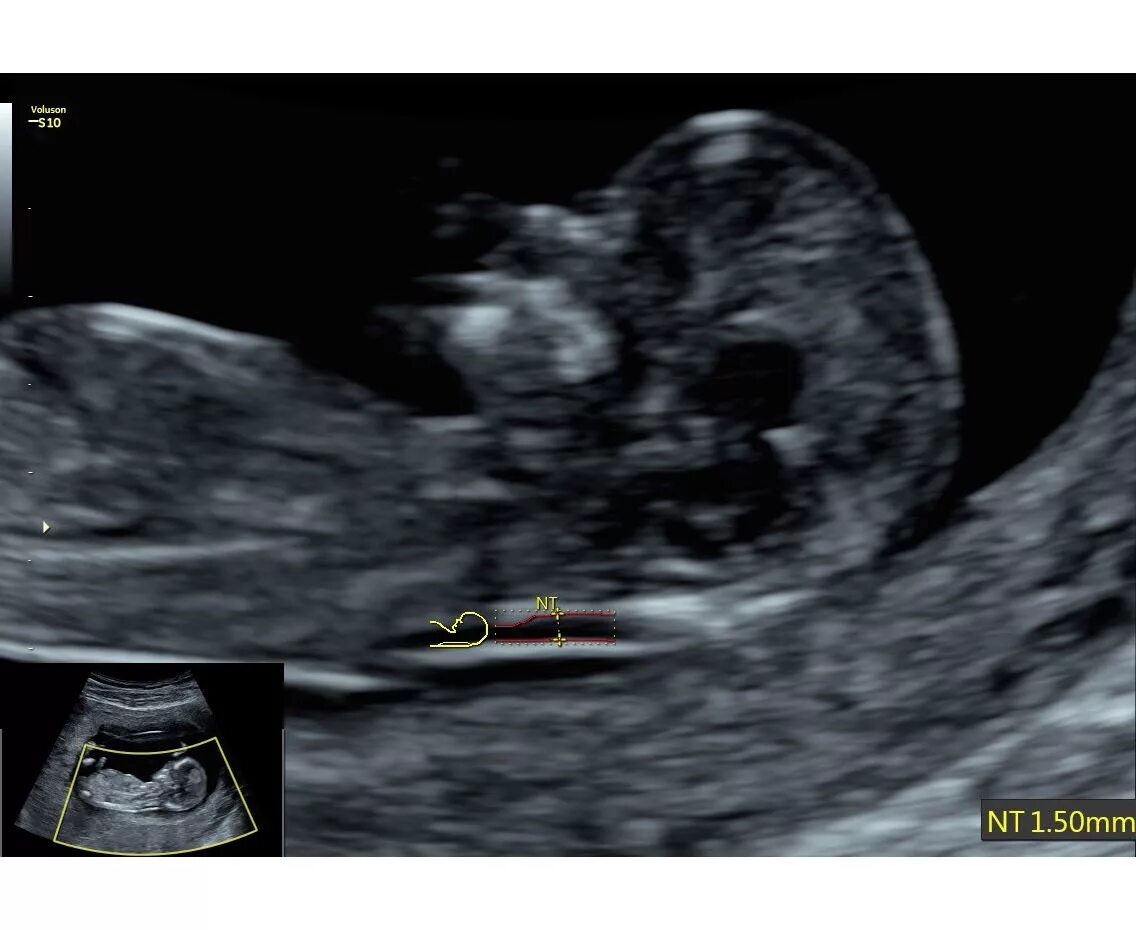

Воротниковое пространство 5